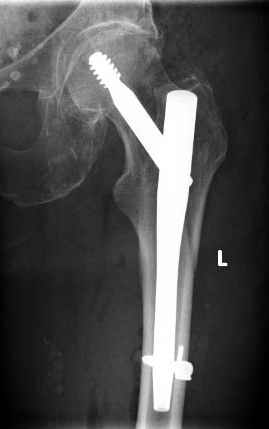

Поступила пациентка 75 лет с пертрохантерным переломом левой бедренной кости. 15 лет назад перелом справа, который прооперировали тогда гвоздем лециуса.

Я его только в книжках видел. Сейчас остеосинтез гамма-нагелем справа. Пациентка стала примером прогресса медицины. Век живи, век учись... Вальдемар Киндсватер.